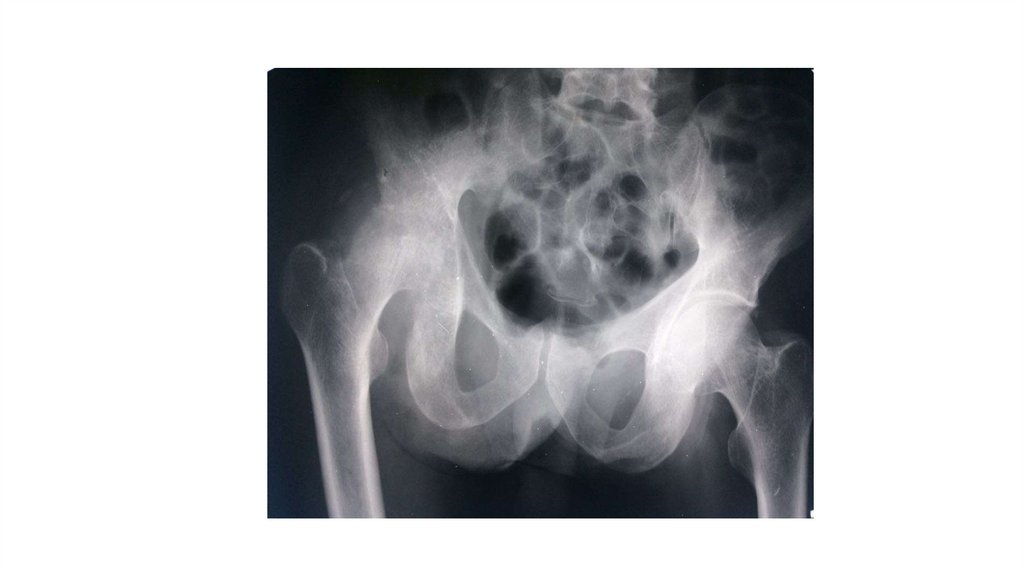

Воспалительные заболевания опорнодвигательного аппарата

«Воспалительные

заболевания опорнодвигательного аппарата»